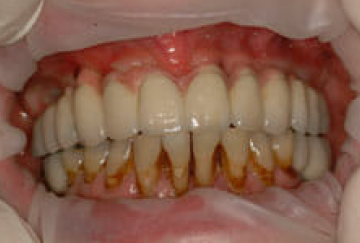

The end result

This picture shows the results of the implant and upper bridge – the patient is also due back soon so can that we can either improve or replace the remaining lower front teeth.

I’m not at liberty to show the ‘before pics’ for this case, however suffice to say – everyone was delighted with the results so far: 12 shiny new implant-bridge teeth in the upper jaw (supported by 7 implants) plus 4 strong new molars to make eating a far more pleasurable experience.